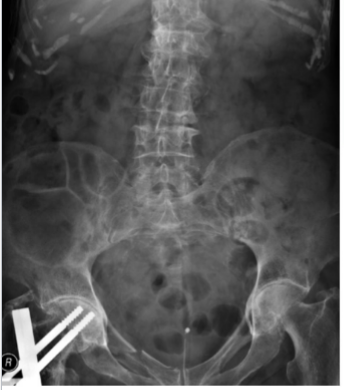

What is this and what type of scan

free gas under the diaphragm 2/2 perforated duodenal ulcer (abnormal bowel gas pattern), ABX